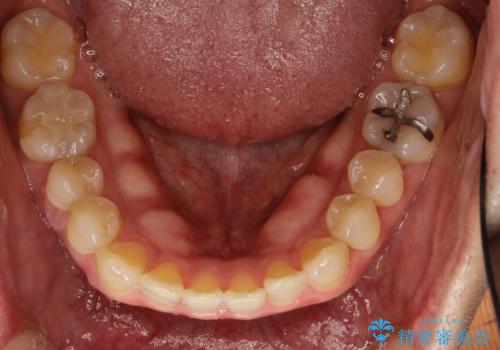

前歯の隙間 インビザラインにて整った歯並びへ

- 前歯の隙間が気になるとのことで来院されました。

インビザラインにて矯正治療を行うこととしました。

下の歯と歯の間にわずかに隙間をつくり、上の前歯の隙間を閉じました。